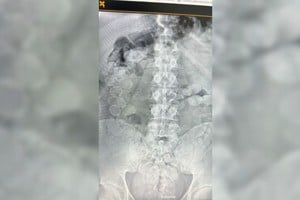

Ahogamiento

En Alto Verde: un bebé en estado crítico tras caerse adentro de un balde con agua